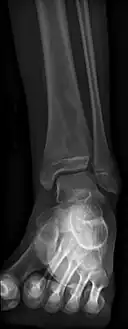

Oval, elliptical, or serpentine radiolucency usually greater than 1 cm surrounded by a heavily reactive sclerosis, granulation tissue, and a nidus often less than 1 cm. The margins often appear scalloped on radiograph. Brodie's abscess is best visualized using computed tomography (CT) scan. Associated atrophy of soft tissue near the site of infection and shortening of the affected bone. Osteoblastoma may be a classic sign for Brodie's abscess.

Periostial reaction along the medial cortex indicates an aggressive lesion. Neoplasm such as Ewing sarcoma and osteomyelitis could both have this plain radiographic appearance. Staphylococcus was recovered at surgery. -